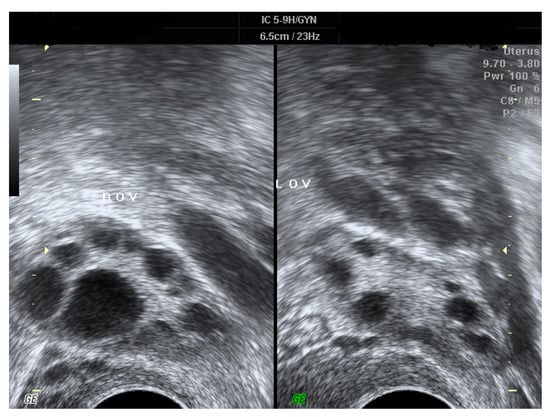

Polycystic ovarian syndrome (PCOS) is the most common endocrine disorder of reproductive-age women [1]. According to the Rotterdam criteria [2], it refers to ovarian dysfunction presented with two of the following three features: chronic anovulation, hyperandrogenism, and special morphologic changes of bilateral ovaries [1,2,3,4,5]. Under ultrasonography, PCOS is characterized by the presence of multiple small follicles in both ovaries and/or increased ovarian volume [2,4] (Figure 1). The prevalence of PCOS is estimated to be 12%–20% among women of reproductive-age [1,4,6,7], and affected women often manifest symptoms and signs including androgen excess, obesity, infertility, and menstrual irregularity [5]. Even though the etiology of PCOS remains unclear and is deemed multi-factorial, current evidence reveals that gene-related resistance to insulin may be the fundamental cause underlying PCOS, with consequent hyperinsulinemia to stimulate excess production of ovarian androgen and to block maturation of follicles [4,8,9,10,11]. More than half of the PCOS patients have coexistent metabolic syndrome [12,13], in whom insulin resistance is a widespread finding and the probability of adult-onset diabetes mellitus is five–eight-fold compared to females without PCOS [13,14]. Additionally, several immunologic disorders, including elevated levels of cytokines [8,15] as well as autoimmune antibodies [16,17,18,19] and immune diseases [16,20], are more common amongst PCOS women. There is an association between PCOS and autoimmune diseases, such as anti-nuclear antibody (ANA) and anti-TPO that have been documented in systemic lupus erythematosus (SLE) and Hashimoto thyroiditis, respectively [21].

Figure 1. The ultrasonic images of PCOS, which are characterized by the presence of multiple small “necklace-like” follicles in both ovaries and/or increased ovarian volume.